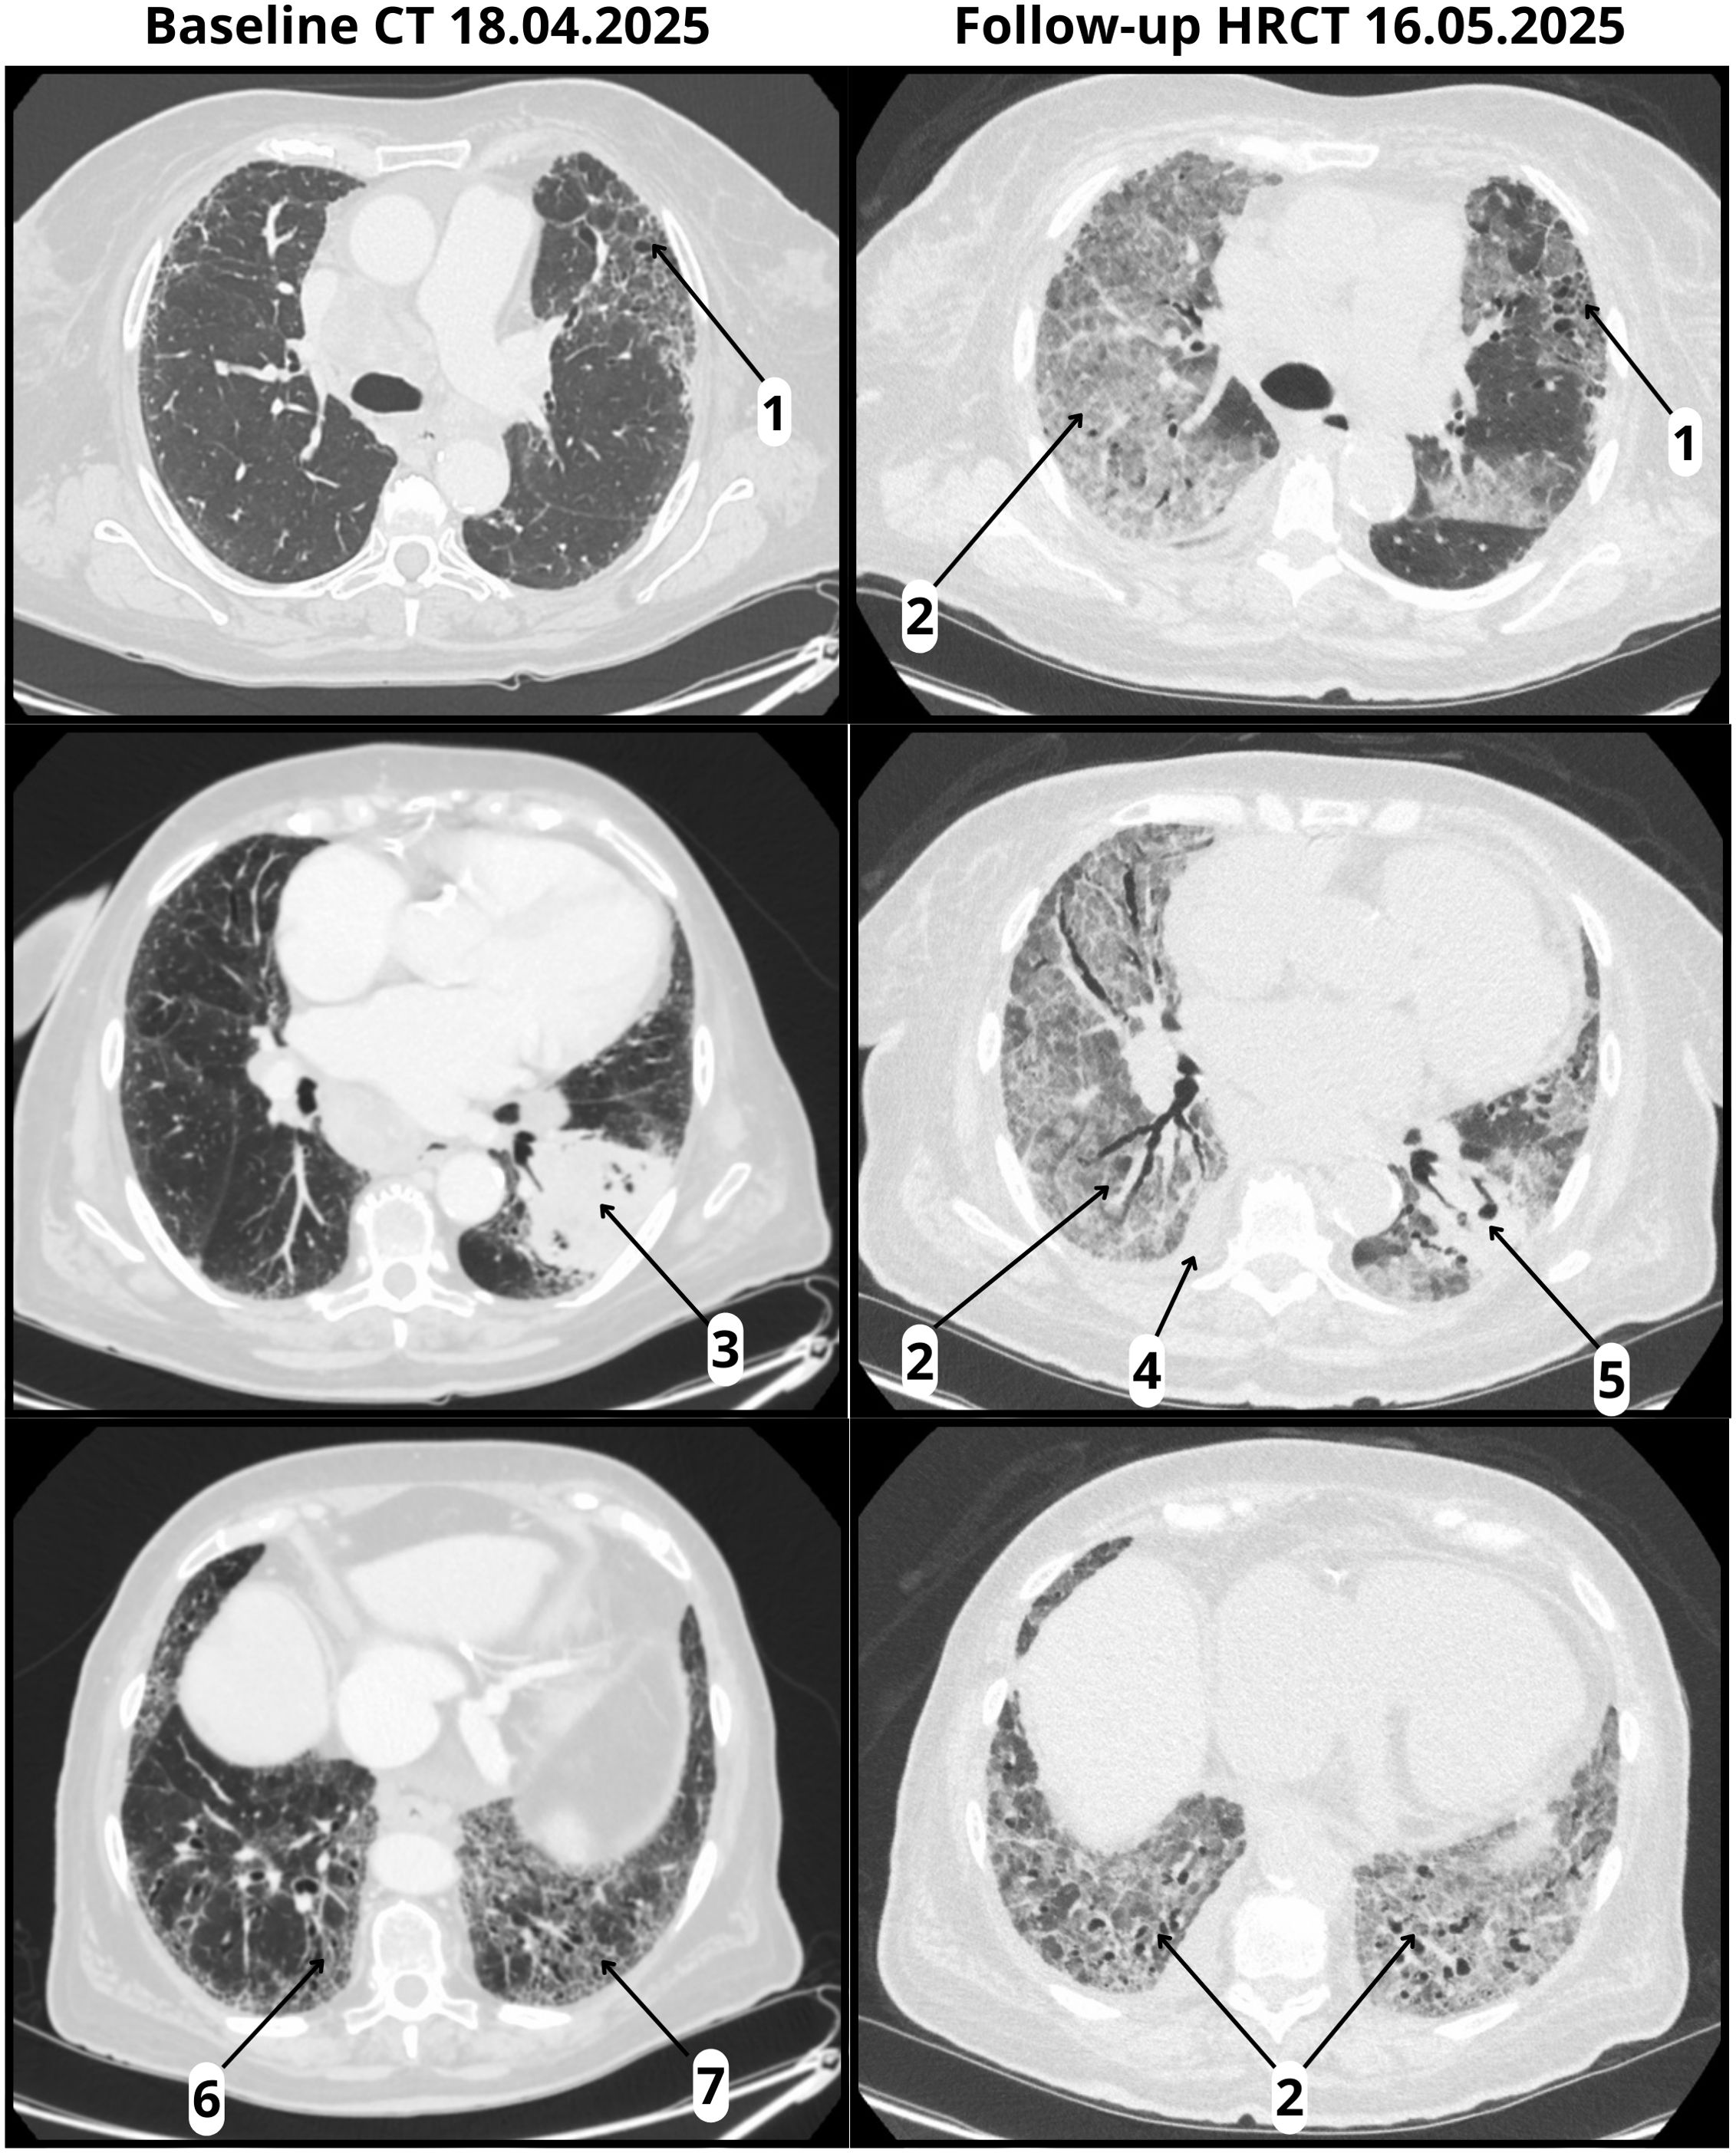

Evaluation included physical examination, laboratory testing, and microbiological studies. Infectious causes were excluded through negative cultures, urinary antigen tests, and multiplex respiratory panel testing. Sputum collection was not feasible because the patient was unable to expectorate, and bronchoscopy with bronchoalveolar lavage was planned but ultimately not performed due to the rapidly deteriorating clinical status. Follow-up high-resolution computed tomography (HRCT) on May 16, 2025, revealed diffuse bilateral ground-glass opacities, a right pleural effusion, and pericardial fluid, all superimposed on a fibrotic background with honeycombing, consistent with a definite UIP pattern. (Figure 1). The imaging findings were radiologically compatible with both acute interstitial pneumonia (AIP) and acute respiratory distress syndrome (ARDS). Since AIP refers to idiopathic acute lung injury in patients without pre-existing ILD, and ARDS is a clinical diagnosis requiring both radiologic and clinical criteria, we interpreted the presentation as consistent with ARDS, according to A New Global Definition of Acute Respiratory Distress Syndrome (15). The differential diagnosis included CIP, infectious pneumonia, tumor progression, and aspiration. Given the temporal association with pembrolizumab initiation, rapid clinical deterioration, radiologic features, and negative infectious workup, a diagnosis of fulminant early-onset CIP was established. The patient’s prognosis was considered poor due to the coexistence of IPF and advanced-stage lung cancer.

Figure 1

CT and HRCT scans showing lung sections with annotations. The left panels exhibit baseline scans from April 18, 2025, with various labels pointing to specific regions. The right panels display follow-up scans from May 16, 2025, with similar labels indicating changes in lung appearance and texture. The comparison highlights differences in lung condition over time.

Figure 1. Baseline CT and follow-up HRCT. Baseline CT (18 April 2025) and follow-up HRCT (16 May 2025, performed 22 days after pembrolizumab infusion): (1) Honeycombing; (2) ground-glass opacities (absent at baseline, new at follow-up); (3) tumor in the left lower lobe with pleural involvement; (4) right pleural effusion (new at follow-up); (5) reduction in tumor size (follow-up); (6) traction bronchiectasis; (7) volume loss.